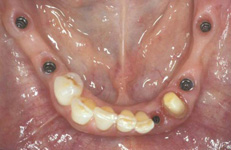

Během let může postupnou ztrátou zubů zůstat v ústech omezený počet zubů, které umožňují držení zubních náhrad.

V důsledku přetížení zbylých zubů např. houpavými pohyb snímacích náhrad dochází k uvolnění těchto zubů a držení můstků a protéz je tak velmi těžké. V těchto případech můžeme pomocí implantátů zvýšit počet pilířů a tím zabránit přetěžování a ztrátě zbylých zubů

> zpět k možným příkladům ošetření